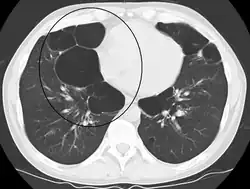

A CT scan is not routinely used except for the exclusion of bronchiectasis.[5] Pulse oximetry measurement of peripheral oxygen saturation is recommended in people with clinical signs of respiratory failure or right heart failure.[5] An analysis of arterial blood is recommended in those with a peripheral oxygen saturation of 92% or less to determine actual blood oxygen level and assess for high levels of carbon dioxide in the blood, which may have therapeutic implications such as need for non-invasive ventilation or oxygen supplementation.[10] WHO recommends that all those diagnosed with COPD be screened for alpha-1 antitrypsin deficiency.[40]

Axial CT image of the lung of a person with end-stage bullous emphysema -

Very severe emphysema with lung cancer on the left (CT scan)

In very severe cases, lung transplantation might be considered.[191] A CT scan may be useful in surgery considerations.[87] Ventilation/perfusion scintigraphy is another imaging method that may be used to evaluate cases for surgical interventions and also to evaluate post-surgery responses.[198] A bullectomy may be carried out when a giant bulla occupies more than a third of a hemithorax.[193]